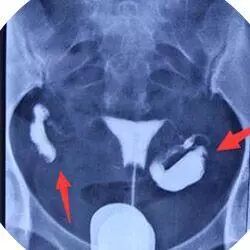

科学检查:输卵管碘海醇造影是目前先进的输卵管堵塞诊断方式,能清晰直观看到输卵管内部情况,定位堵塞部位、类型。